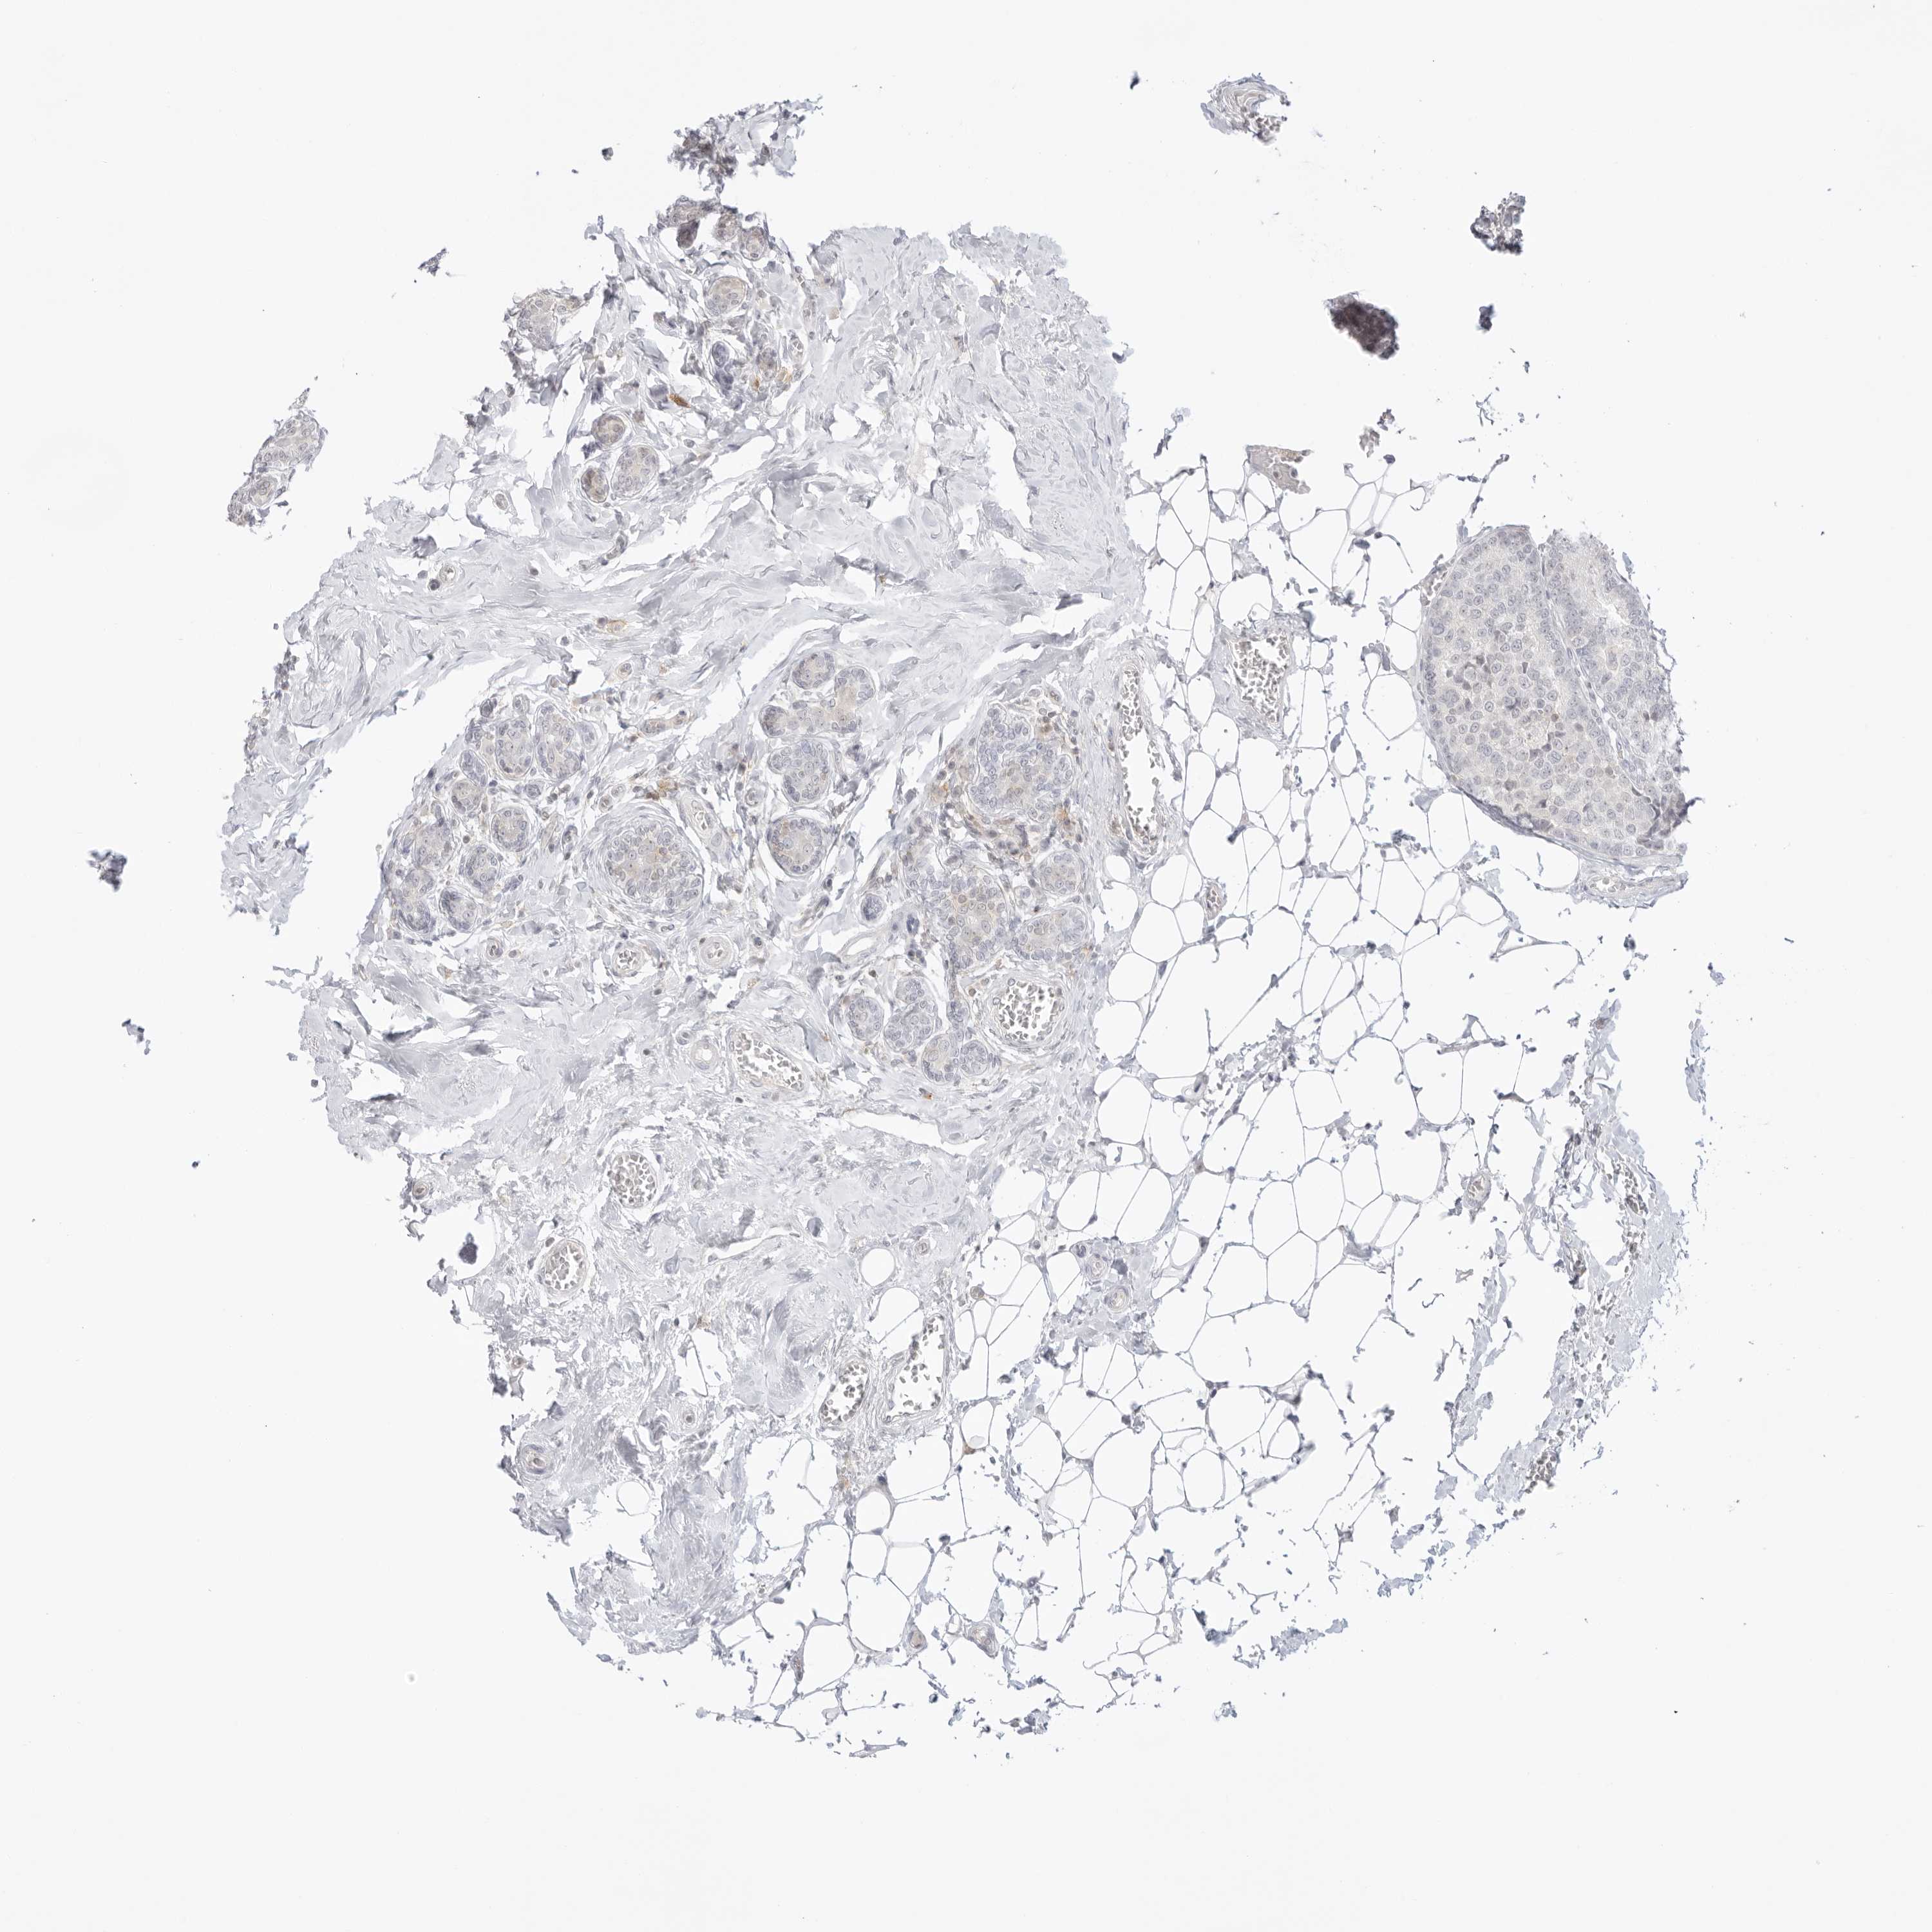

CANCER BREAST CANCER Show tissue menu

BRCA TCGA BRCA VALIDATION PROTEIN EXPRESSION